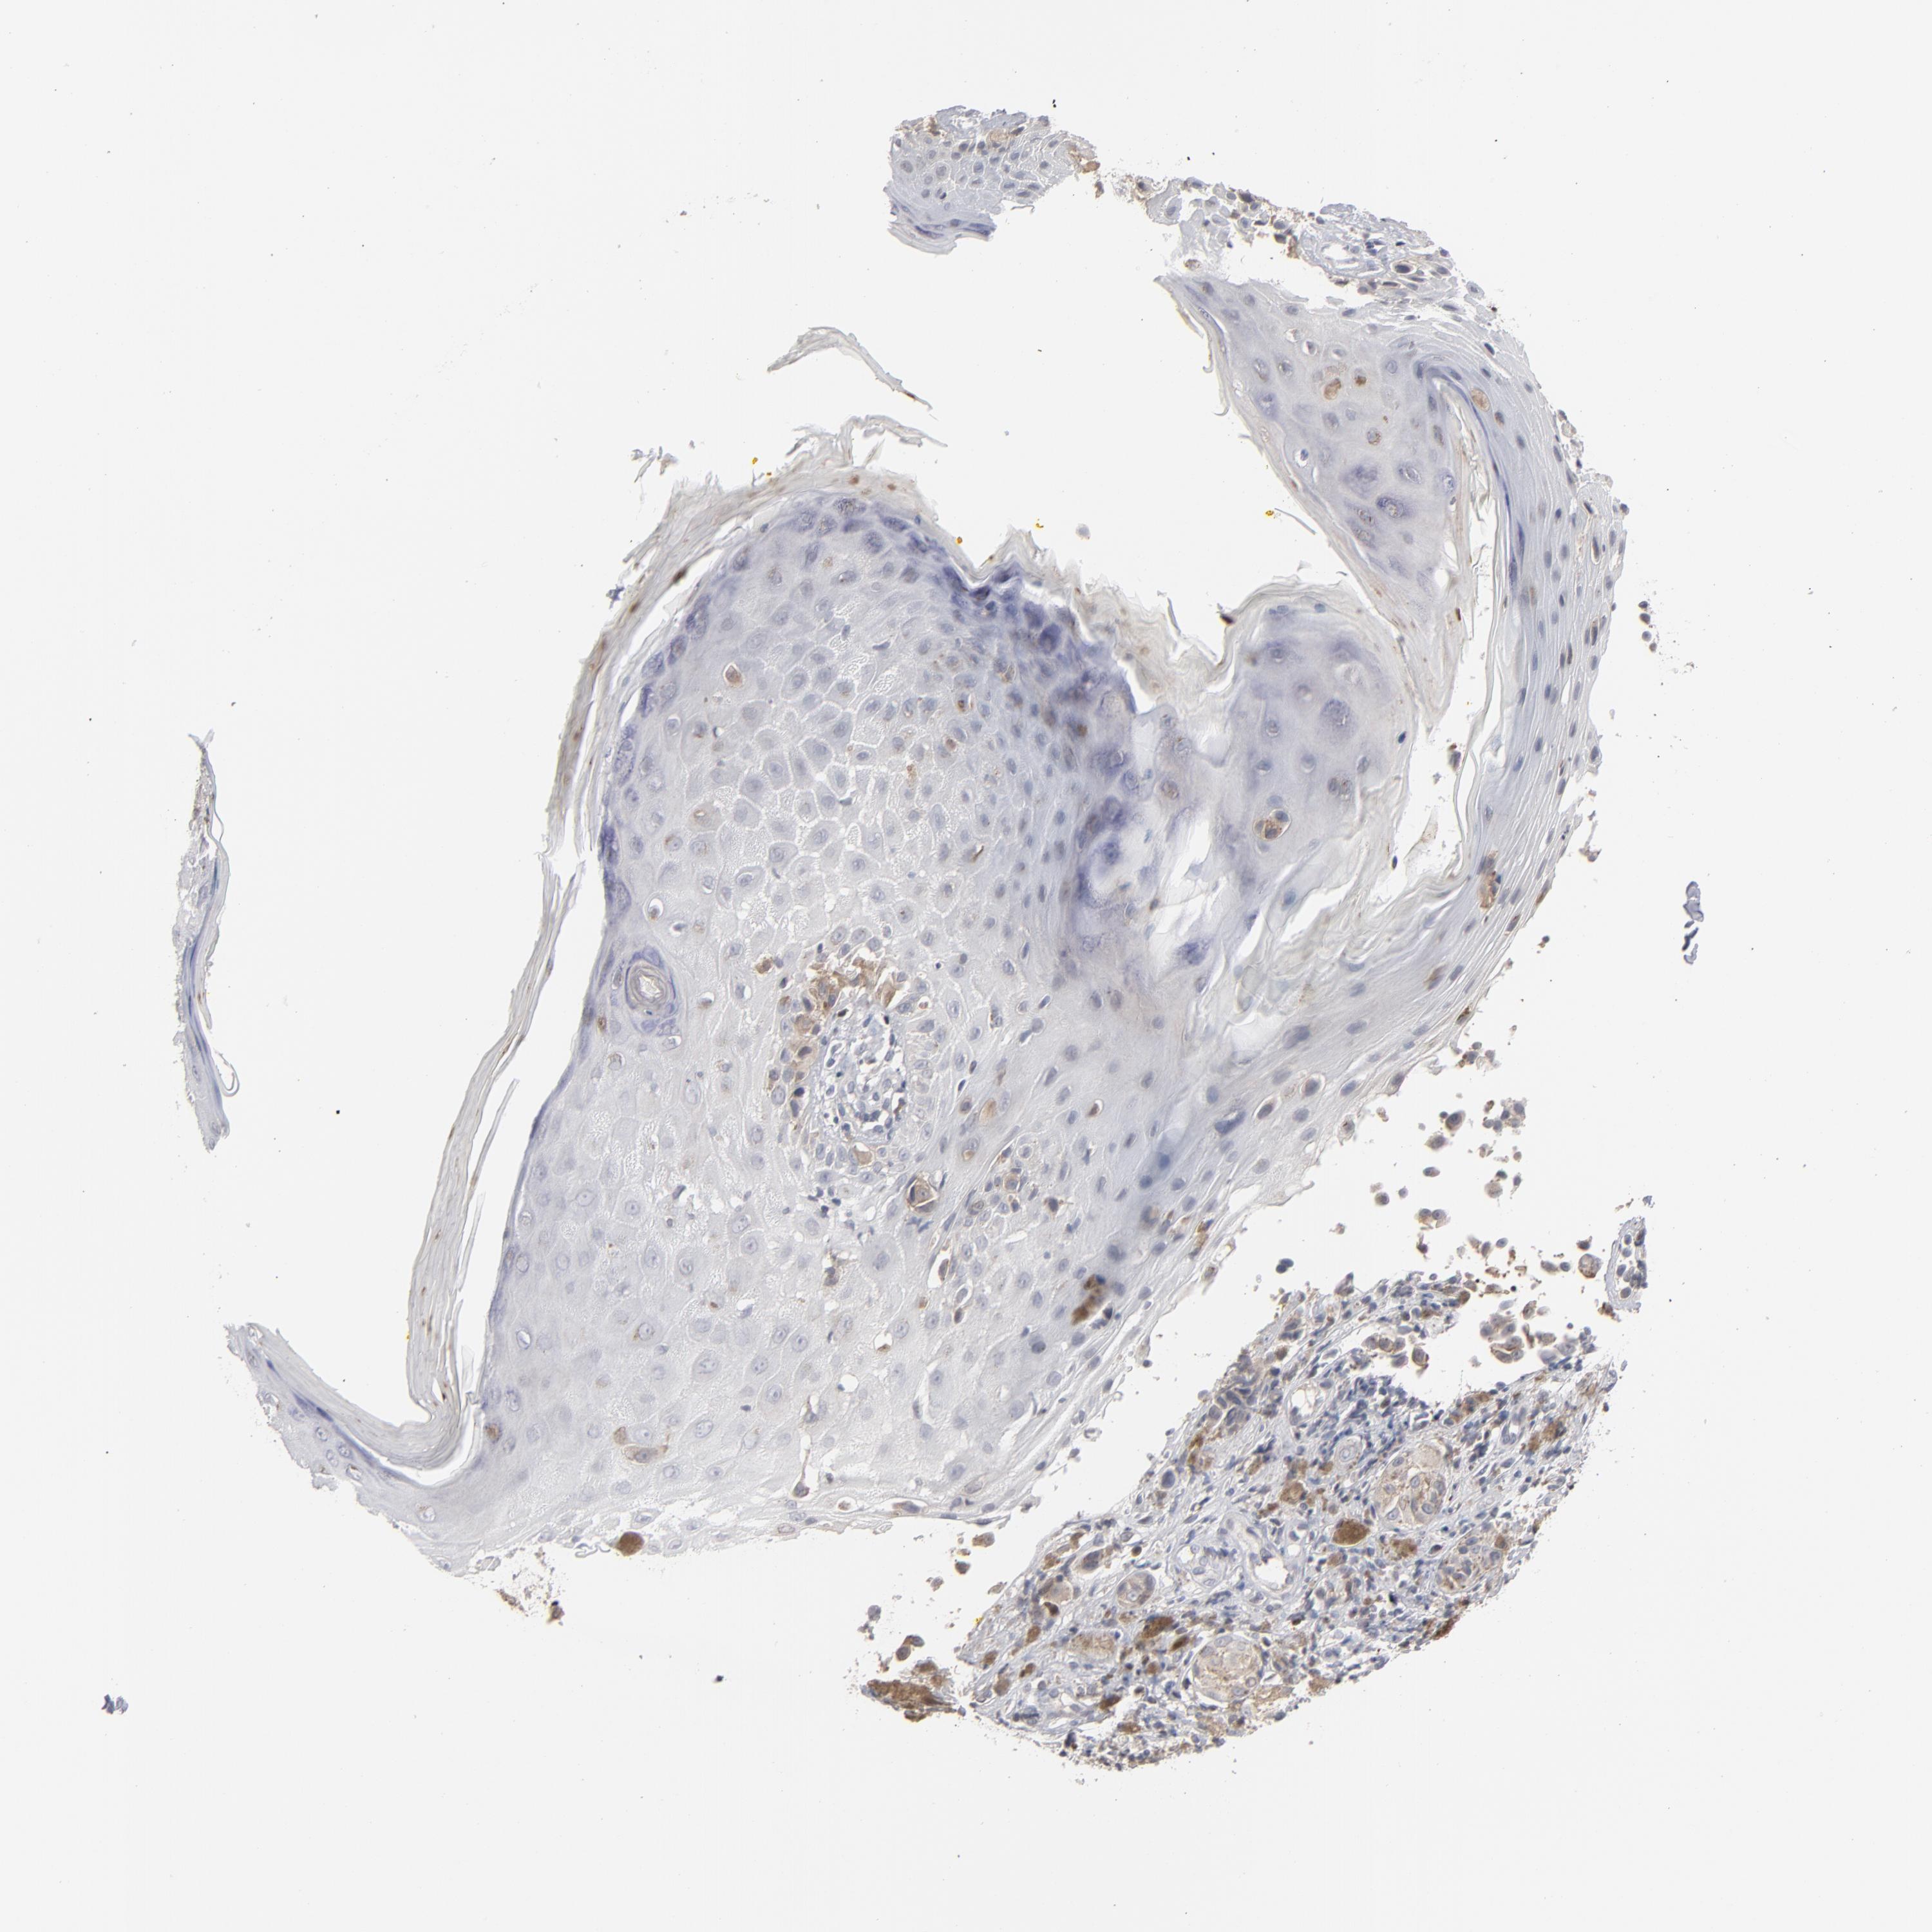

MELANOMA - Protein expressioni

A mouse-over function shows sample information and annotation data. Click on an image to view it in a full screen mode. Samples can be filtered based on level of antibody staining by selecting one or several of the following categories: high, medium, low and not detected. The assay and annotation is described here.

Note that samples used for immunohistochemistry by the Human Protein Atlas do not correspond to samples in the TCGA dataset.

Antibody stainingi

Antibody staining in the annotated cell types in the current human tissue is reported as not detected, low, medium, or high, based on conventional immunohistochemistry profiling in selected tissues. This score is based on the combination of the staining intensity and fraction of stained cells.

Each image is clickable and will lead to virtual microscopy that enables deeper exploration of all samples and also displays staining intensity scores, fraction scores and subcellular localization as well as patient and tissue information for each sample.

Antibody HPA001860

Antibody CAB013108

Staining

High

Medium

Low

Not detected

Intensity

Strong

Moderate

Weak

Negative

Quantity

>75%

75%-25%

<25%

None

Location

Nuclear

Cytoplasmic/membranous

Cytoplasmic/membranous,nuclear

Malignant melanoma, NOS

Malignant melanoma, Metastatic site